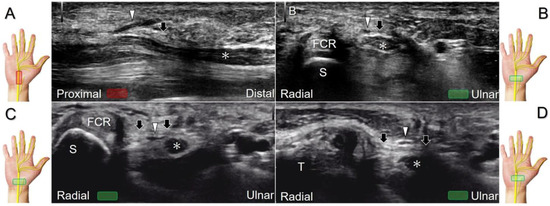

Scanning Technique

To locate the Guyon’s canal, the transducer is placed along the axial plane on the volar wrist with the forearm supinated. This will reveal the ulnar nerve and artery within the canal (Figure 13A). To investigate the nerve’s long axis, the transducer is rotated 90 degrees. By moving the transducer toward the finger, the superficial and deep branches can be seen. Between the pisiform and hamate, the superficial and deep branches (along with their accompanying vessels) can be visualized as separated by the fibrous arch of hypothenar muscles, respectively (Figure 13B) [39].

The superficial branch divides into two palmar digital nerves. They run superficially along the little finger and half of the ring finger. The deep branch, on the other hand, can be observed between the flexor digiti minimi brevis and opponens digiti minimi muscles before it penetrates the deep aspect of the palm (Figure 13C). By pivoting the transducer, the physician can display the long axis of the deep branch, extending all the way to the segment within the adductor pollicis muscle (Figure 13D).

Figure 13. Sonographic imaging (short-axis view) shows the ulnar nerve within the Guyon’s canal (A), separation of branches beside the pisohamate hiatus (B), deep branch of the ulnar nerve located between the hypothenar muscles distal to the hook of the hamate (C). Long-axis view (through pivoting the transducer) shows the segment of the deep branch within the adductor pollicis muscle (D). Arrowhead: ulnar nerve; white arrows: superficial branch of the ulnar nerve; black arrows: deep branch of the ulnar nerve; orange arrow: branch of the ulnar nerve to the abductor digiti minimi; *: pisohamate ligment MN: median nerve; UA: ulnar artery; P: pisiform; H: hook of hamate; A: artery; L: lumbrical muscle; FDM: flexor digiti minimi brevis muscle; Opp DM: opponens digiti minimi muscle; AbDM: abductor digiti minimi muscle; AdP: adductor pollicis muscle.